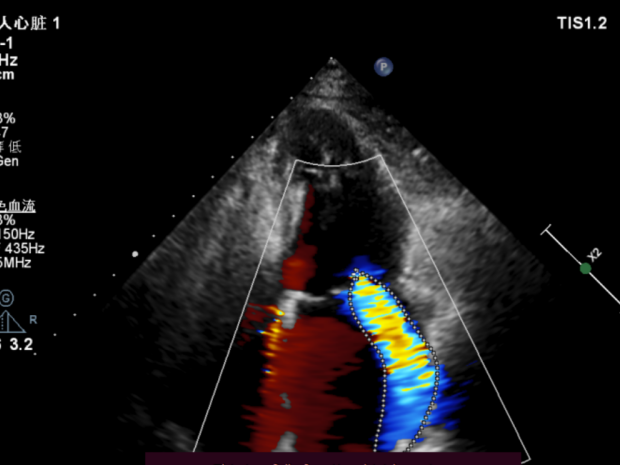

主诉:活动后气促8年余;二尖瓣轻度脱垂并中重度反流

二尖瓣轻度脱垂并中重度反流

患者全麻后在超声和射线引导下穿刺股静脉-房间隔,器械顺利到达病变的二尖瓣区域,成功完成二尖瓣夹合后,患者二尖瓣反流即刻显著下降,左房压力即刻减低,预示着患者的临床症状将会得到明显改善。